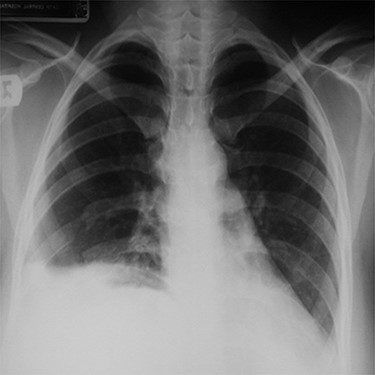

The patient was prepared for surgery. The chest was opened through a right posterolateral thoracotomy. The right hemi-diaphragm was found to be absent and the liver was lying high up in the right thorax with its inferior surface adherently facing the pericardium. The right lung was collapsed, and the transverse colon and the stomach were also found in the right hemi-thorax inferiorly. The liver was carefully mobilized from the pericardium and the herniated organs were successfully reduced into the abdomen. After excision of the thin hernia sac, the right diaphragm was reconstructed using a polypropylene mesh. The right lung expanded well at the end of the procedure. Postoperative chest x-ray showed full inflation of the right lung (Fig. 3).

A post-operative chest x-ray showing full inflation of the right lung.